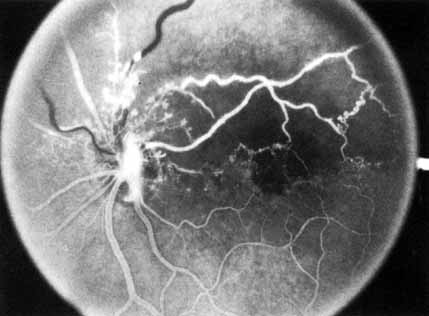

The intravenous fluorescein angiogram pattern of an ischemic central retinal vein occlusion is usually characterized by a delayed filling time of the venous tree of the retina, capillary and venous dilation, and extensive leaking of fluorescein into the retina, particularly in the macular area and in the area adjacent to the larger venous trunks and capillary nonperfusion (see Fig. 3C and 3D; Figs. 4 and 5). Microaneurysms may not be noted at the time of initial occlusion, but are usually manifest shortly thereafter. Late-phase photographs show patchy extravascular areas of fluorescence and staining of the retinal veins. Fluorescence in the macula indicates capillary leakage and edema; this not only may account for much of the initial visual loss in the acute phase, but may also eventually result in permanent structural changes. Intravenous indocyanine green videoangiography may also be helpful in showing the arterial and venous flow alterations in this condition.322

Fig. 4 Fluorescein angiogram after moderately ischemic central retinal vein occlusion. A. Early venous phase. The capillary bed is dilated and engorged. Punctate areas of fluorescence represent microaneurysms or small areas of capillary leakage. B. Midvenous phase. There is considerable delay in venous return and an increase in and coalescence of punctate areas of extravascular fluorescence. C. Late venous phase. Fluorescence staining along the vein margins and scattered areas of capillary nonperfusion (arrow) are present.